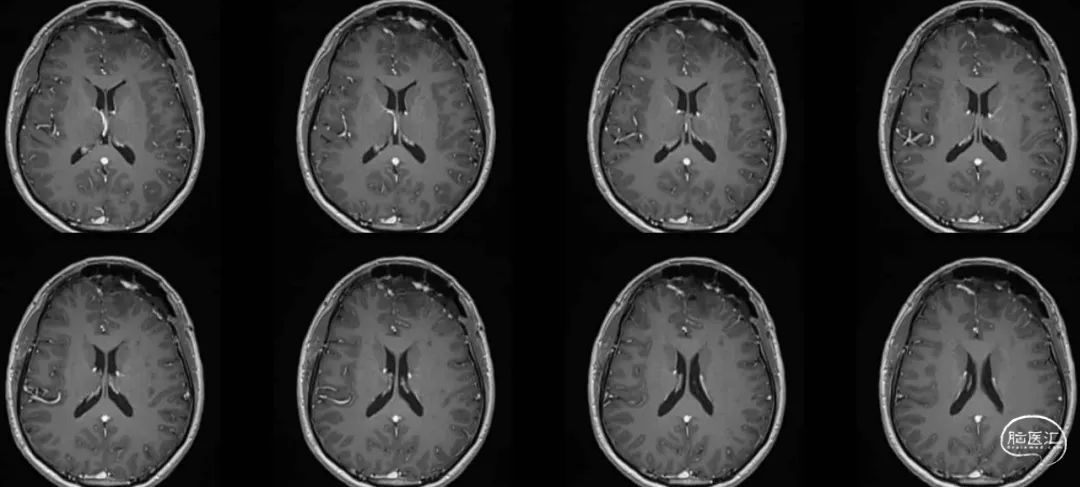

MRI

术后头颅MR:肿瘤全切